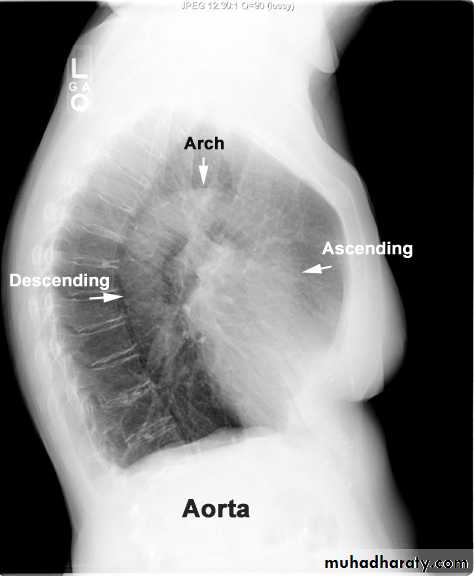

Lateral view position